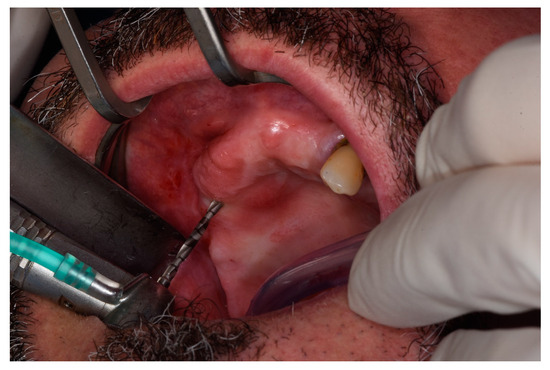

2.2. Surgical Procedures and Post-Operative Care